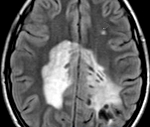

Электроэнцефалография показывает признаки диффузного поражения головного мозга: снижение альфа-активности и дезорганизация ритма; Эпилептиформная активность часто определяется. При исследовании спинномозговой жидкости было обнаружено увеличение уровня гамма-глобулина на фоне снижения удельного веса фракции альбумина. Наиболее информативным типом инструментальной диагностики является МРТ головного мозга. Болезнь Шильдера подтверждает наличие по крайней мере одного большого или пары слитых участков демиелинизации в белом веществе.

Многие неврологи используют критерии с.M. определить окончательный диагноз. Poser 1985: наличие по данным МРТ 1-2 круглых зон демиелинизации размером не менее 2х3 отсутствие надпочечниковой патологии; исключение любой другой патологии головного мозга (внутримозговая опухоль, диссеминированный энцефаломиелит, инсульт ); соблюдение нормы уровня жирных кислот в сыворотке крови; выявление в плотном срезе зон диффузного хронического рассеянного склероза. В некоторых случаях только гистологическое исследование тканей головного мозга пораженного участка позволяет отличить лейкоэнцефалит Шильдера от лейкодистрофии.